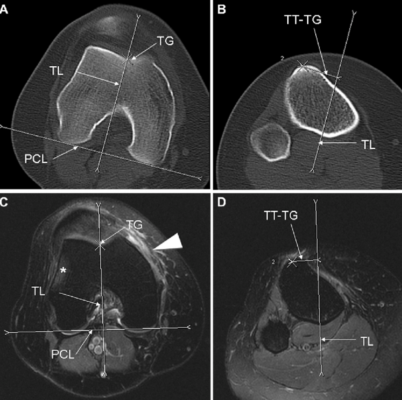

Valutazione dei parametri anatomici

Attraverso l’imaging, in particolare RM e TC nei casi selezionati, è possibile misurare parametri chiave nella valutazione dell’instabilità rotulea, tra cui:

- altezza rotulea

- distanza tibial tuberosity–trochlear groove (TT–TG)

- profondità e forma della troclea femorale

- allineamento complessivo dell’arto inferiore

Questi parametri consentono di distinguere le forme prevalentemente traumatiche da quelle a base costituzionale e di pianificare eventuali trattamenti chirurgici correttivi.

Tomografia computerizzata (TC)

La TC trova indicazione in casi selezionati, soprattutto quando è necessario uno studio accurato dei rapporti ossei o una pianificazione chirurgica dettagliata. Sebbene comporti un’esposizione a radiazioni ionizzanti, la TC può fornire informazioni utili sulla morfologia trocleare e sull’allineamento rotuleo in condizioni dinamiche specifiche.